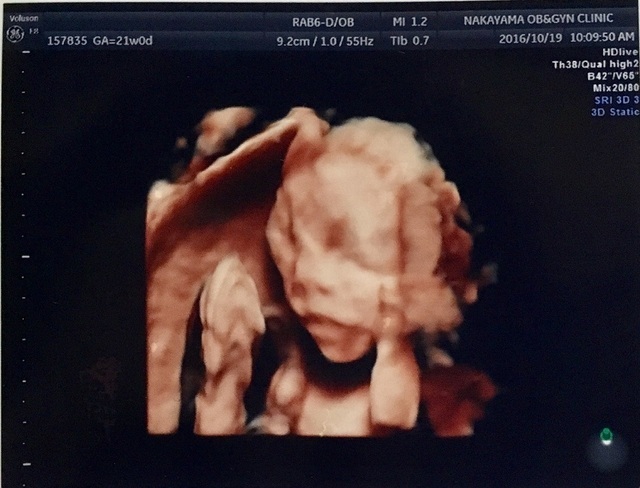

21週0日(21w0d・女の子)|晴香 さん(23歳)

エコー写真撮影時のエピソード:

エコーではいつも手で顔を隠していたので、なかなか顔を見ることができませんでした。この写真は、初めて子どもの顔がエコーに映った時のものです。

パパ似だなぁとか言いながら、夫婦で何度も見た写真です。この写真を見ると出産の不安は無くなり、会えるのがとても楽しみになりました。